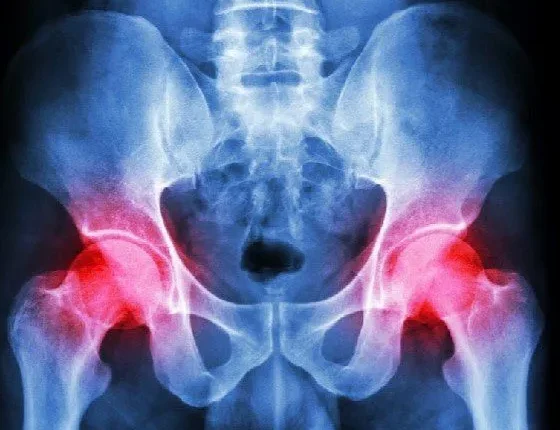

Η οστεοαρθρίτιδα εμφανίζεται όταν υποστεί φθορά ο αρθρικός χόνδρος, που καλύπτει την επιφάνεια των οστών μέσα στην άρθρωση με αποτέλεσμα αυτή να μένει απροστάτευτη.

Τα συμπτώματα της οστεοαρθρίτιδας

Ο χόνδρος είναι ένας ανθεκτικός και ολισθηρός ιστός που καλύπτει τις καταλήξεις των οστών, προκειμένου να είναι ομαλή η κίνηση όταν δύο οστά δημιουργούν μια άρθρωση. Οταν ο χόνδρος καταρρεύσει η ομαλή κίνηση των οστών παύει να υφίσταται, αφού πλέον αυτά έχουν απωλέσει το «μαξιλάρι» προστασίας τους και αναγκαστικά τρίβονται μεταξύ τους. Τα συμπτώματα συνήθως περιλαμβάνουν πόνο στις αρθρώσεις με οίδημα και το εύρος της κίνησης στην προσβεβλημένη άρθρωση μπορεί να μειωθεί σοβαρά. Επιπλέον, με την πάροδο του χρόνου τα οστεόφυτα (αυτά που ο περισσότερος κόσμος γνωρίζει ως «άλατα» -που δεν έχουν σχέση με το αλάτι που τρώμε), μπορεί να σχηματιστούν περιμετρικά της άρθρωσης.